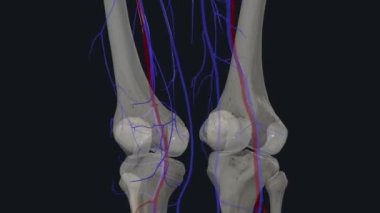

SağlıkkanİlaçkalpStetoskopTedaviHastalıkbiyolojiGöğüsorgİyileştiriyorvenanatomibelirtileriobstrüksiyonarterkapillerkasılmaAtriumGöğüs kemiğiaortKalp kriziKalp kasıGöğüs Ağrısıkalp zarınıKan damarıStentkan akımıacil tedaviKoroner artersol ventrikülSağ ventrikülkalp ilacıdiyaframdanKalp kapakçığıkardiyovasküler sistemSol atriyumPulmoner dolaşımSistemik dolaşımPulmoner arterSağ atriumsemilunar valvepulmoner venbicuspid valvepapillary musclecardiac septumcardiac wallheart catheterisationBenzer İçerikler